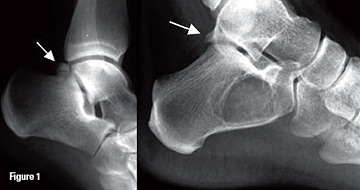

Je ne vois pas très bien où est l'os trigone, qui n'apparait pas sur le schéma..

Est-ce que qqun pourrait me le réexpliquer ?